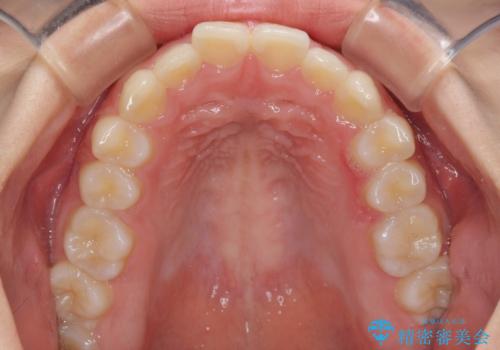

前歯のデコボコと突出感 インビザラインによる矯正治療

- 上下前歯のデコボコと、上顎前歯の突出感を気にして来院された患者様です。

インビザラインによる上下歯列の側方拡大と後方移動、IPR(歯と歯の間を削る)にるスペースの獲得により歯列を整えることとしました。

毎日22時間以上しっかりとマウスピースを装着していただいたので、スムーズに治療が進みました。歯と歯の間を削ることでうまくスペースコントロールでき、1年強で終えることができました。